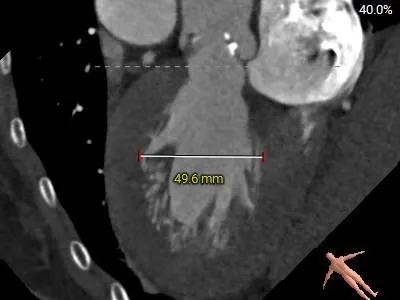

术前CT分析

主动脉根部测量

Annulus

20.1mm

LVOT

19.9mm

钙化积分

322mm3

STJ 26.3mm

高16.7mm

AAO

33.4mm

L-30.6mm R-27.5mm

N-29.5mm

-

三叶瓣,RL/RN高位纤维融合,瓣环偏大

瓣环直径约20.1mm,直筒型流出道

瓣叶增厚,中度钙化